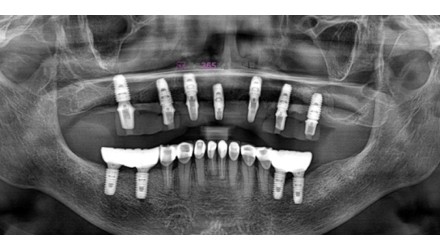

심*복 임플란트 시술 사례

전체 임플란트

2024.12.05

치료 전

2025.05.30

치료 후